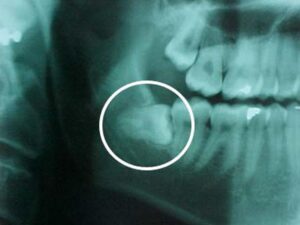

They come in between the ages of 17 and 25. When a tooth is unable to fully enter the mouth, it is said to be “impacted.” In general, impacted teeth are unable to break through the gums because there is not enough room. Nine out of ten people have at least one impacted wisdom tooth.

Impacted inside the jaw

Damage to neighboring teeth